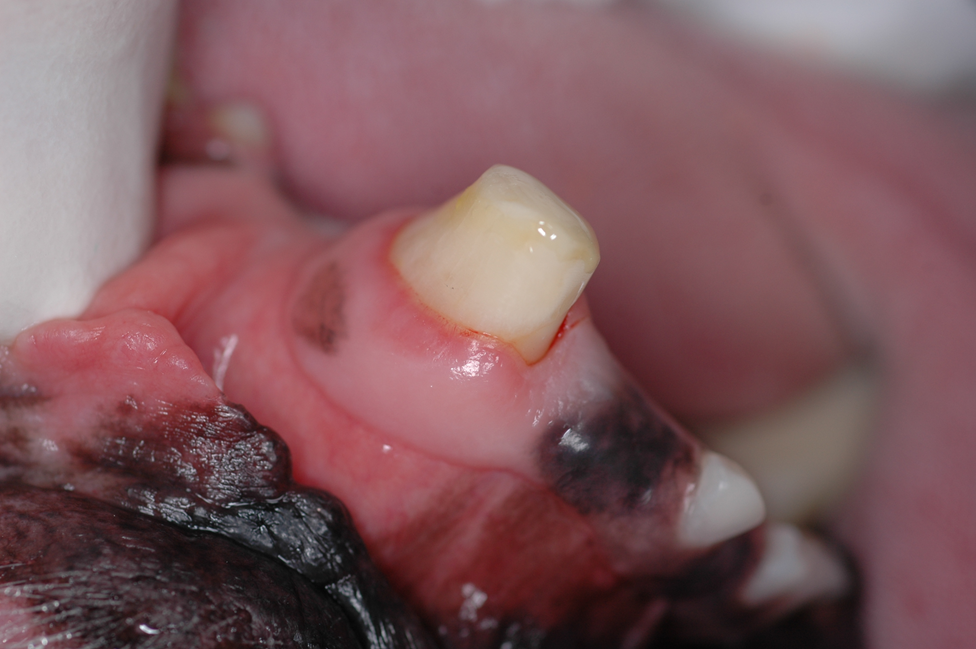

Broken teeth need to be treated immediately.  A tooth that has been broken less than 48 hrs can be saved with a procedure called a “Vital Pulpotomy.”   After 48 hrs., treatment options are root canal therapy or extraction.  Since our pet friends rely heavily on their teeth, saving them is a better and less painful option (root canal therapy).   Leaving a broken tooth in the mouth without treatment causes unnecessary, prolonged oral pain. Finally, a discolored tooth is a dead tooth.  A recent study indicated that 92% of all discolored teeth are non-vital (dead).  Saving those teeth via root canal therapy +/- a crown is highly recommended for those teeth that are deemed strategic (all canine teeth, maxillary 4th premolars and mandibular 1st molar teeth)